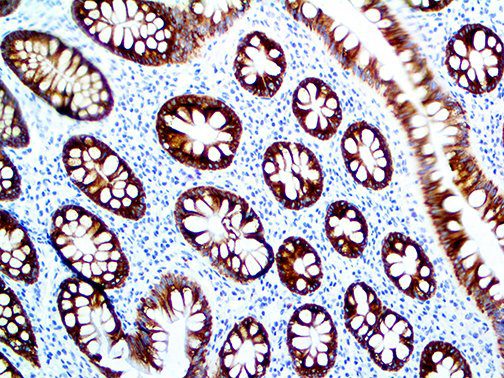

This activation induces inflammatory monocytes to highly express IL-6, starting a localized and then systemic cascade effect that results in hyperproduction of IL-6, which accelerates the inflammatory process. Because IL-6 also increases vascular permeability, excessive levels cause blood vessels to become very leaky. This, along with clotting factors released from vascular endothelial cells, stimulates the coagulation cascade, resulting in microthrombosis (tiny clots), which leads to ischemia and tissue death of the kidney, intestines, heart, liver, brain and extremities.